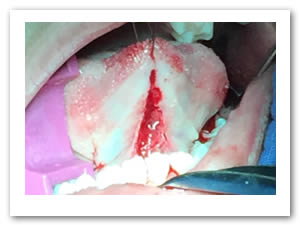

• Se colocó anestesia tópica y se infiltró localmente (lidocaína con epinefrina de 1: 100 000 al 2 %) a cada lado del frenillo lingual bloqueando nervio lingual bilateralmente. (Figuras 1 y 2).

Figura 1. Anestesia Local a cada lado del frenillo.

Figura 2. Anestesia Local del nervio lingual bilateralmente

• Se pasa una sutura sin anudar en la punta de la lengua para traccionar la misma y facilitar las maniobras quirúrgicas. Posteriormente se utilizan dos pinzas de mosco, una curva y una recta pinzando el frenillo en su borde superior e inferior para limitar sus bordes. Figuras 3 y 4.

Figura 3. Sutura sin anudar en punta de la lengua

Figura 4. Pinzado del frenillo